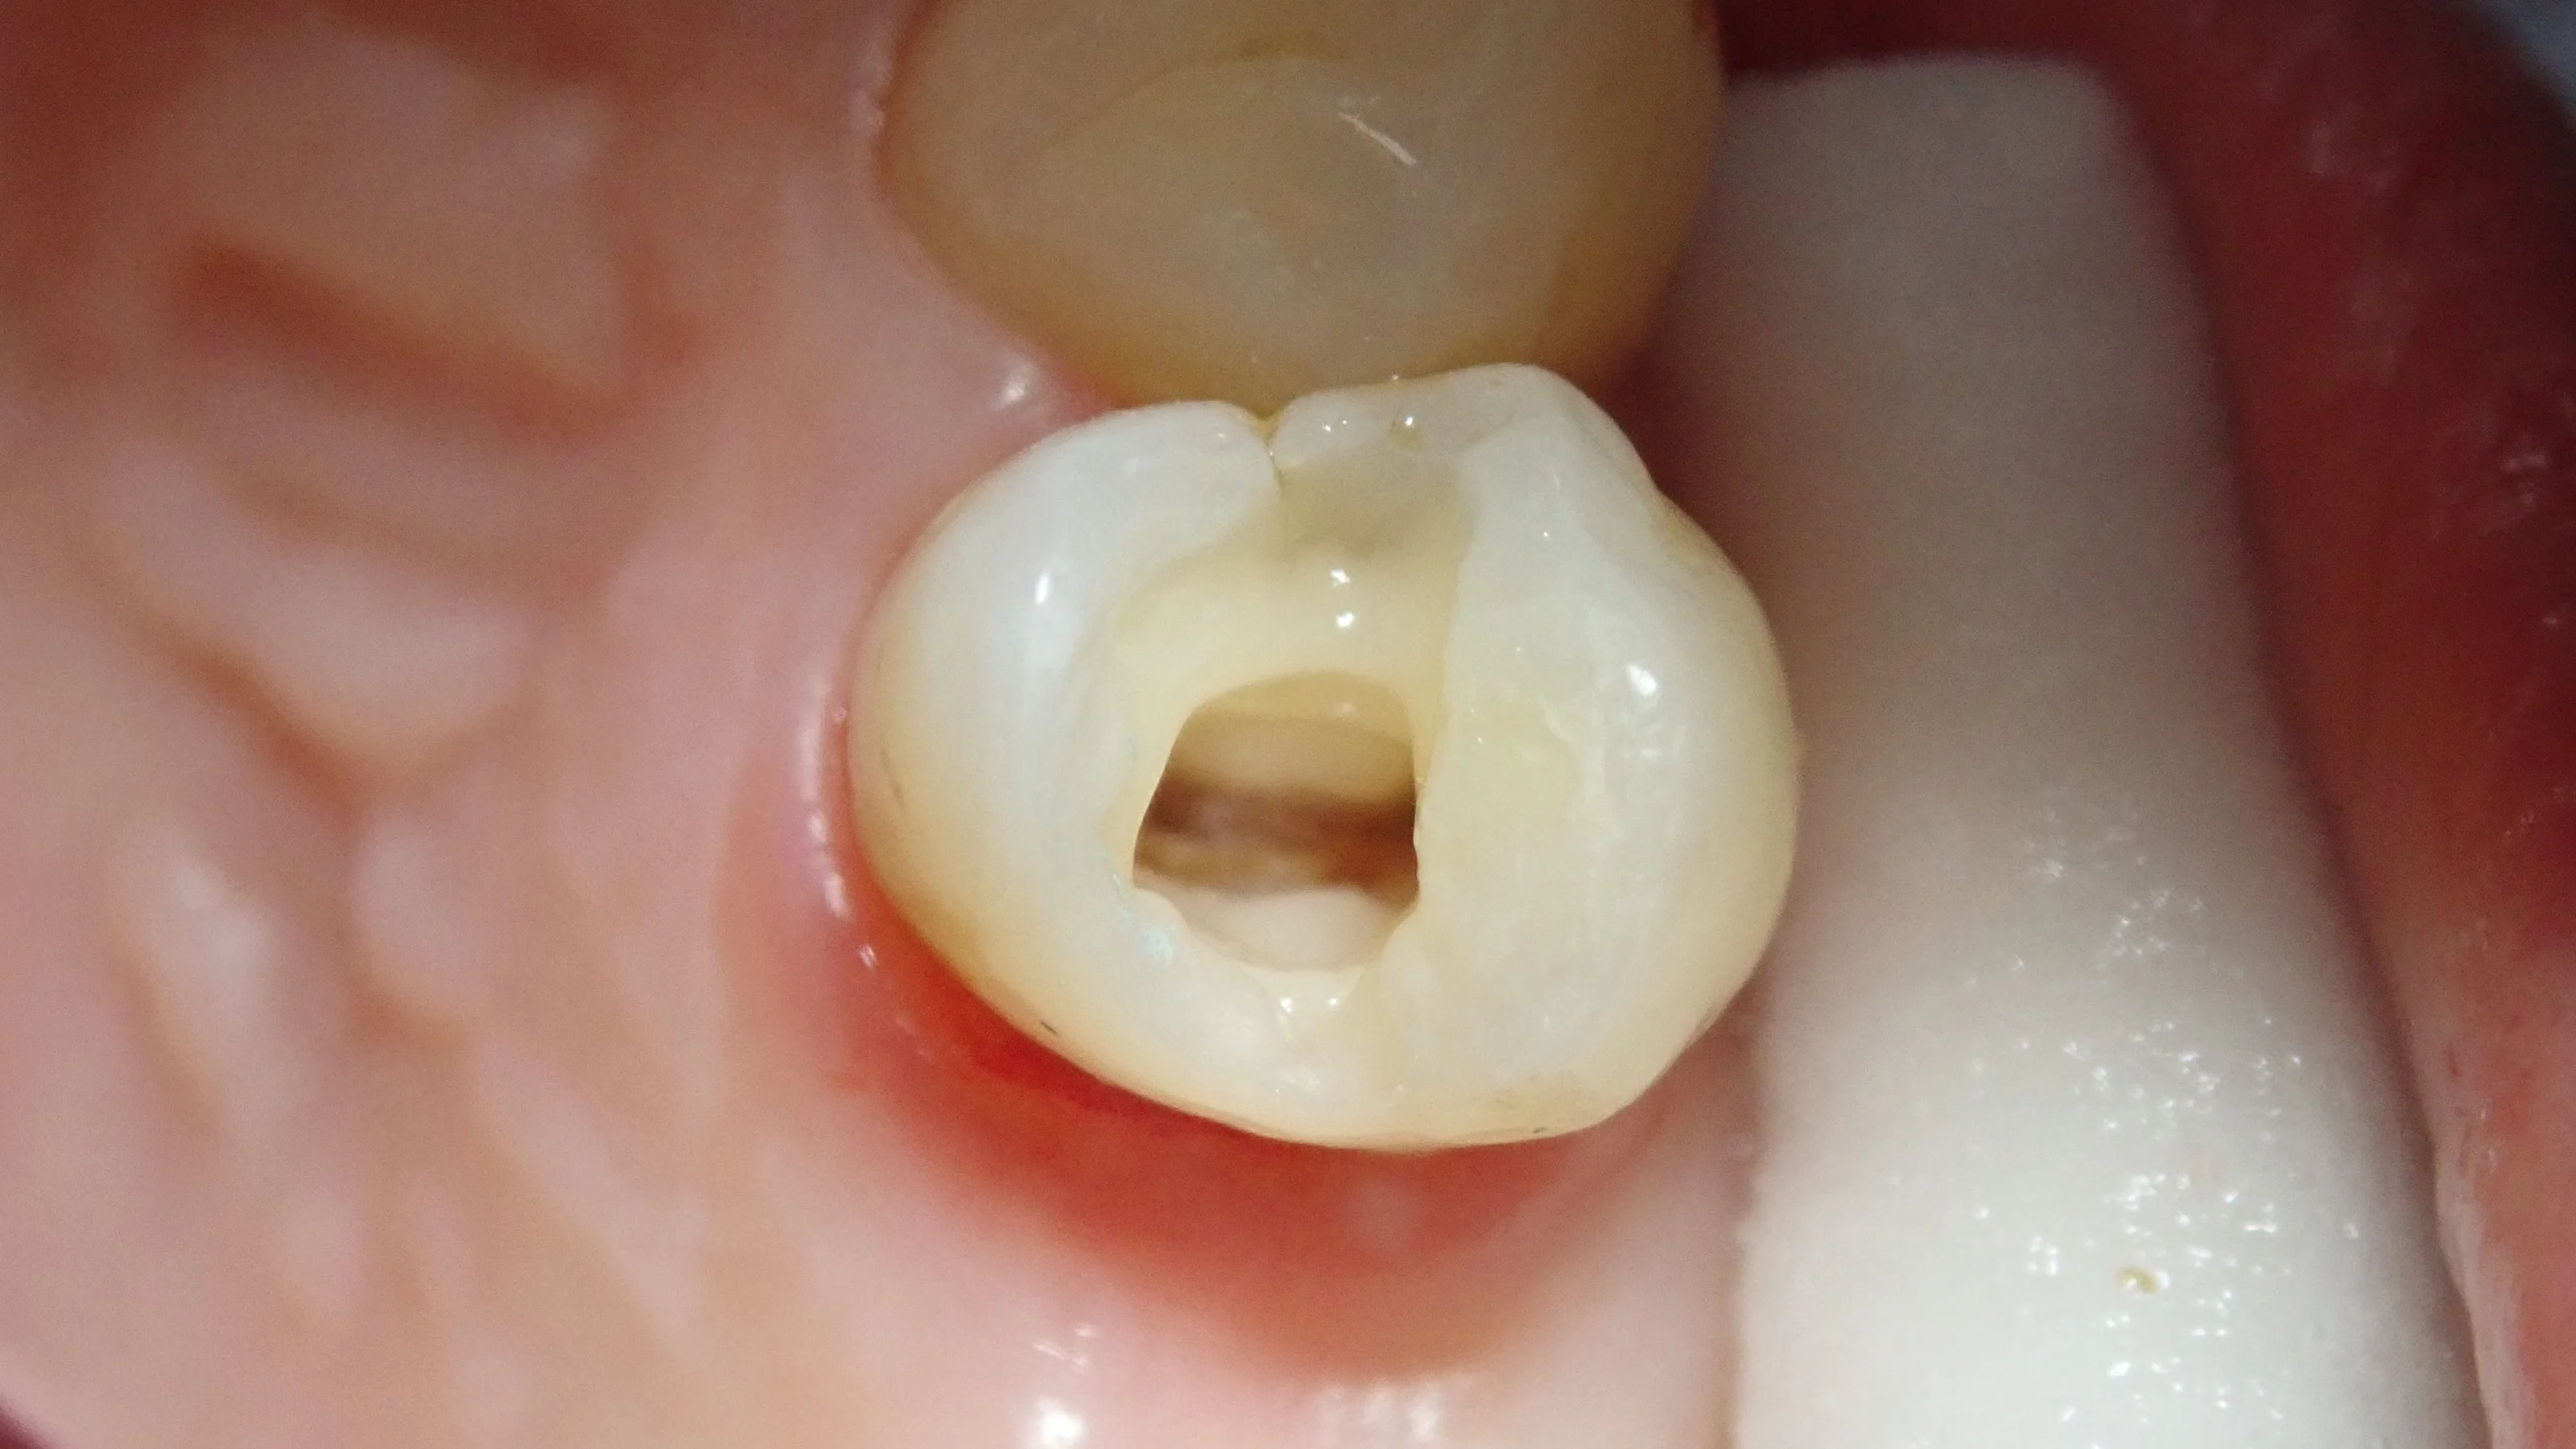

術前のレントゲンです。

若干、根尖(根の先)が黒くなっており、膿が溜まっているように見えます。

また、詰めたものと歯の間に大きなギャップがあり、その中で虫歯が進んでいます。

神経の治療になる可能性が非常に高いことを説明して治療をスタート。